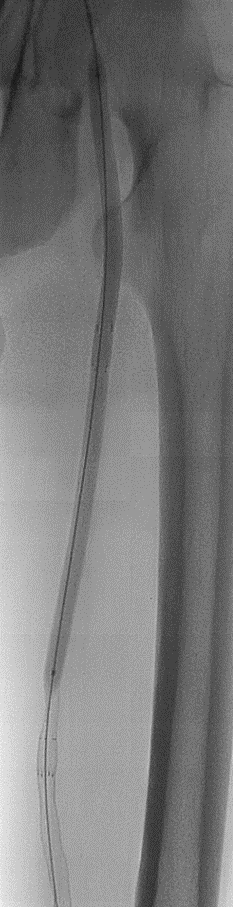

预扩:充分预扩张至关重要,需逐级使用高压球囊,最终达到 6mm 直径,以获得足够的管腔。

支架植入:遵循“由远及近”原则,先放置远端 DES,再覆盖中段 VB,最后处理近端。利用 Eluvia 的可调节性优化重叠。

后扩:常规使用 6mm 高压球囊进行后扩张,确保支架充分贴壁和管腔获得。